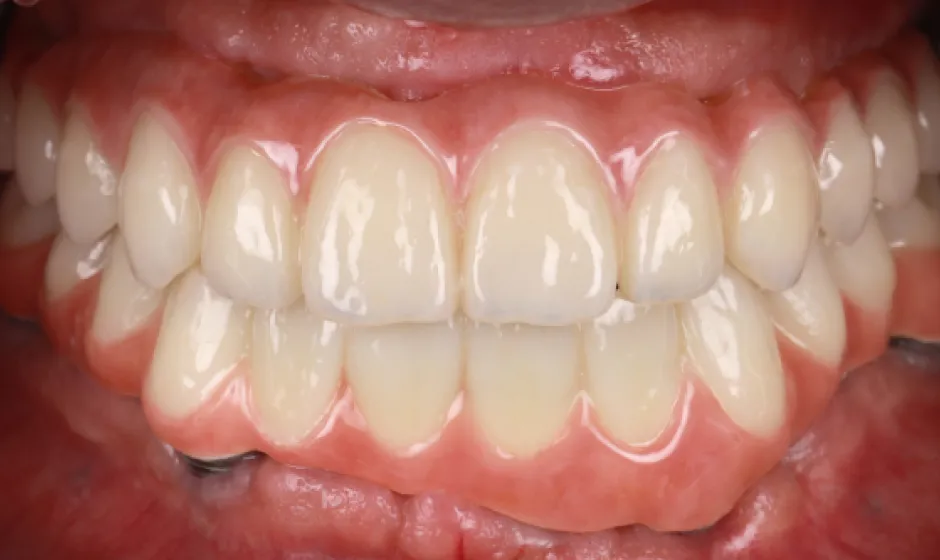

症例2

- 治療名

- 【高度審美形成】歯間乳頭再建術

- 患者様

- 40代女性

- 執刀医

- Dr. 大杉

- 治療期間

- 約1年

- 治療費

- 300,000円(税込)

- リスク

- 移植組織の定着後も、メンテナンスが予後を大きく左右します。

特に歯間ブラシの不適切な使用や過度なブラッシング圧は組織の退縮を招くため、術後は当院の指導に基づいた厳密なプラークコントロールが必要です。